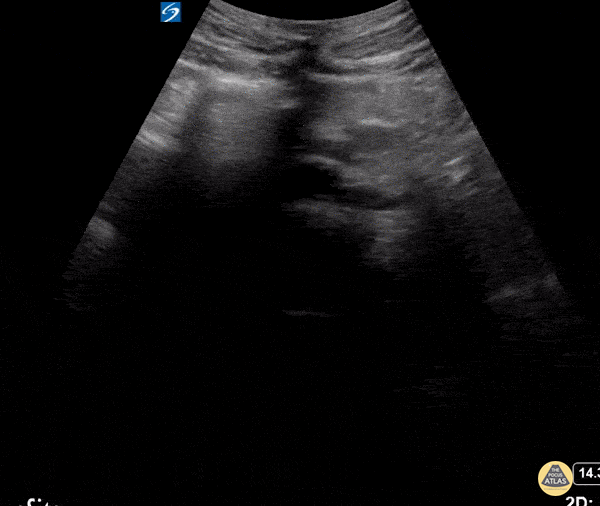

Incidentally found horseshoe kidneys in pelvis joined at the isthmus. Dr. Coneybeare